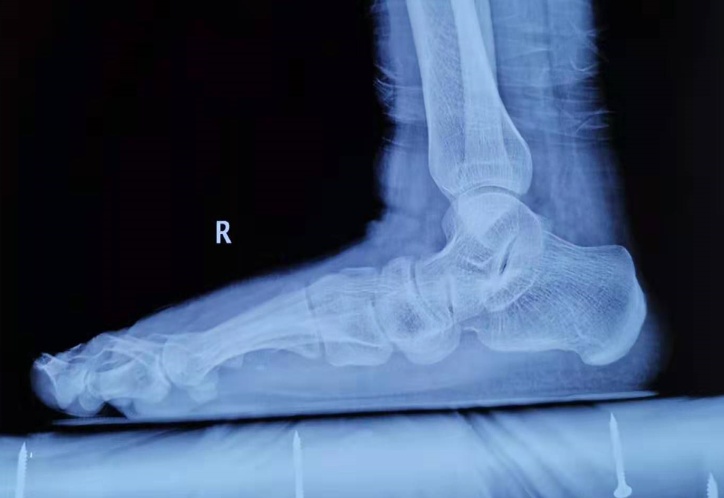

近日,骨科四病区王凯主治医师在汪玉良主任医师、刘京升主任医师的指导下,完成了1例复杂平足手术,手术顺利,患者术后恢复良好。该手术的成功完成,标志着我院对疑难足踝疾病的诊治水平进一步提高,同时为我省足踝外科专业发展积累了宝贵经验。